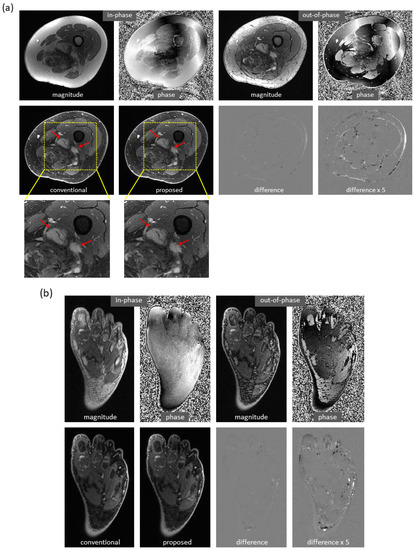

Using the proposed method, water/fat swaps that appeared in reference images were mitigated in the predicted images. Figure 4 demonstrates some examples with minor water/fat swaps. In Figure 4a, B 0 inhomogeneities (in a slice far away from the isocenter) led to artifacts in a reference image of the knee; the artifacts did not appear in the predicted image. Here, tumor and adjacent nerve were well delineated in the predicted image, which is critical for surgical planning. In Figure 4b,c, a more complete separation of water and fat signals was achieved in the predicted images of the knee and arm. In Figure 4d, local water/fat swaps in a reference image of the foot were largely compensated in the predicted image. Notably, these images of the arm and foot were inferred using models trained with only knee data, and the robustness of the proposed approach to out-of-distribution data was demonstrated.

Figure 4. Mitigation of slight water/fat swaps. (a) Artifacts in an off-isocenter reference image of the knee (blue arrows), which were introduced by severe B 0 inhomogeneities, were automatically compensated in the predicted image. Here, tumor (red arrows) and adjacent nerve (green arrows) were well separated in the predicted image. (b) Water–fat separation was improved in the predicted image of the knee as compared to the reference image, which had regions of error (arrows). (c) More complete water–fat separation was observed in the predicted image of the arm, even if the deep learning model was trained with only knee images. (d) Some local water/fat swaps that appeared in the reference image of the foot did not occur in the predicted image. It is of note that the images (c,d) demonstrated the robustness of the approach to out-of-distribution data.